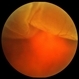

- subhyaloid hemorrhage, acute

- Acute subhyaloid hemorrhage CF.